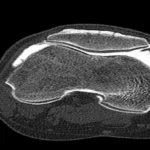

CT scan of a joint

A CT scan of a joint is a test that provides images of a specific joint in the body. This test is commonly ordered when a patient is experiencing symptoms related to a joint.

During a CT scan of a joint, the patient lies down on a table that slides into the CT machine. The machine takes multiple images from different angles and uses computer processing to create a 3D image of the joint. The test is painless and usually takes less than 30 minutes to complete.